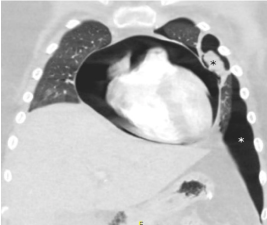

On PICU day 13, our patient developed sudden onset of sharp, substernal chest pain. Chest radiograph and repeat CT of the chest confirmed newly developed PPC in the setting of new cavitary lesions suggestive of aspergillomas (Figure 2). Echocardiogram revealed normal biventricular function and was negative for pericardial effusion or tamponade. Antifungal therapy was transitioned to Voriconazole in light of these clinical findings. Her respiratory status remained stable and serial chest radiographs showed stable PPC.

Figure 2. Aspergilloma adjacent to pericardium (black asterisk) with pneumopericardium (black arrow)

Figure 3. Chest CT demonstrating pneumothorax (white asterisk) with adjacent aspergilloma (black asterisk) and expanding pneumopericardium